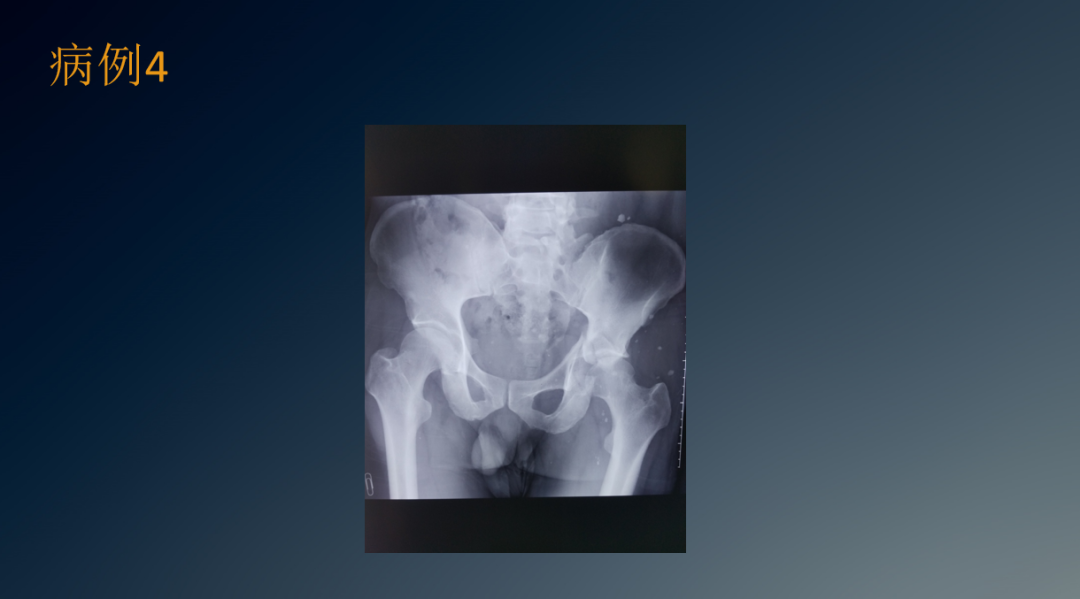

临床病例

髋臼骨折治疗包括保守治疗和手术治疗,除患者基本情况外,主要根据骨折类型和形态进行选择。

髋臼骨折保守治疗适应证有骨折无移位、关节稳定等。治疗方法为牵引3~4周,部分负重4~6周,然后开始完全负重。

髋臼骨折手术治疗适应证有难复性脱位、不稳定性骨折、髋臼顶移位>2mm、关节内骨折、坐骨神经损伤、股骨骨折及膝关节损伤等。手术治疗禁忌证有全身情况差、骨质疏松症、严重粉碎性骨折、伤口污染、术者缺乏外科手术经验、手术设施不足等。